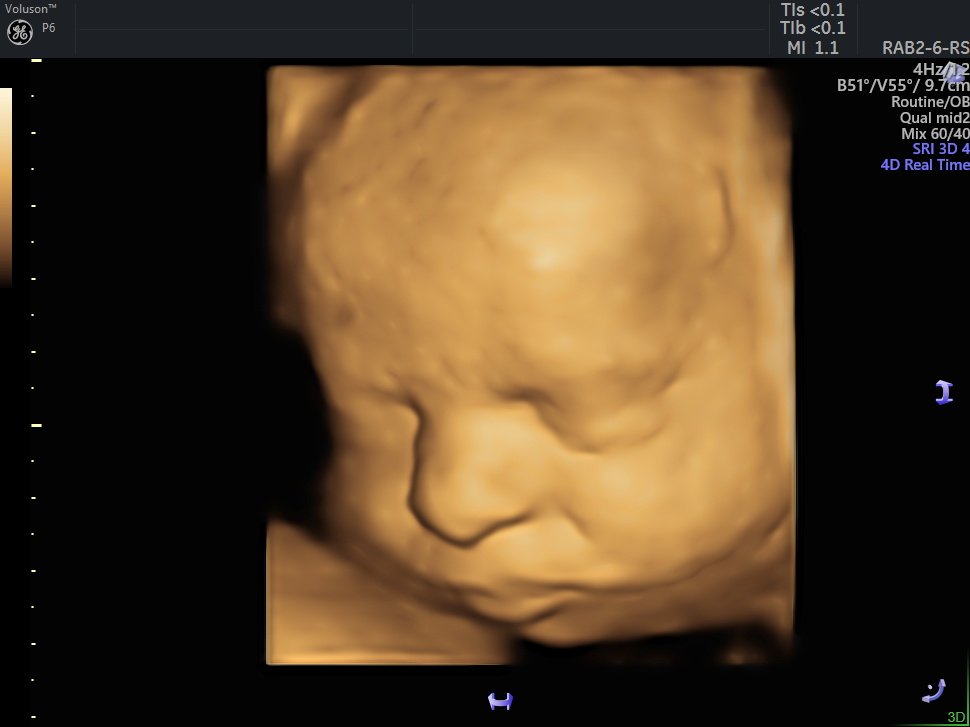

4 Boyutlu (Renkli) Ultrason ve Doppler Ultrasonografi

4 D Ultrasonografi